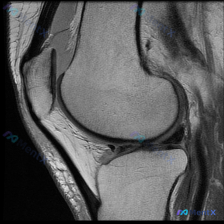

看到这个病例挺有代表性的,整理出来和大家分享一下思路。 病例基础信息 这是一张膝关节矢状位T1加权序列MRI影像,用户提出问题:观察图像是否存在软骨异常。 先给大家整理影像评估的基本结果: 1. 骨骼结构:股骨远端、胫骨近端、髌骨皮质连续,骨髓信号未见异常高低信号,关节面形态基本正常 2. 半月板:...

看到这个挺有代表性的读片病例,整理一下资料和分析思路分享给大家。 病例基础信息 这是一份单张膝关节MRI轴位T1加权序列影像,临床怀疑存在软骨异常,要求读片分析。 影像学读片结果 解剖结构评估 1. 骨性结构:髌骨形态完整,皮质连续,骨髓信号无异常;髌股关节对合关系大致正常,无半脱位;股骨远端滑车区...

今天整理了一个很有启发意义的读片病例,问题是临床怀疑膝关节软骨异常,只给了一张矢状位T1加权MRI,我们一起来梳理整个分析过程。 病例影像基础信息 这是一张膝关节矢状位T1加权像(T1WI),我们先把基础解剖评估说清楚: 1. 骨骼结构:股骨远端、胫骨近端骨皮质连续,无骨质破坏或骨折,关节间隙正常,...

今天遇到一个有意思的读片问题:只给了一张膝关节轴位MRI,问这里有没有软骨异常,整理一下分析思路分享给大家。 基本病例/影像信息 提供的是膝关节单张轴位MRI扫描图像,可识别的解剖结构包括:前方的髌骨、中部的股骨内外侧髁与髁间窝、髌股关节间隙,以及周围部分软组织。 客观影像所见 1. 软骨结构:髌骨...

看到一个很有讨论意义的膝关节影像病例,整理出来和大家分享一下。 病例基本信息 核心问题:临床怀疑存在膝关节软骨异常,仅提供单张膝关节MRI T1序列轴位影像进行分析。 影像学读片结果 这张影像为髌股关节层面的轴位T1加权像,读片结果如下: 1. 骨骼结构:髌骨、股骨内外侧髁形态完整,皮质骨连续,松质...

最近遇到一个有意思的读片病例:临床怀疑髌股关节软骨异常,但给出的单张T1加权轴位MRI却没看到明确病灶,整理一下整个分析思路分享给大家。 一、病例影像基础信息 这是一份膝关节MRI检查的T1加权轴位(横断面)图像,扫描层面位于髌股关节水平,先整理一下基础读片结果: 1. 解剖结构确认:前方为髌骨,后...